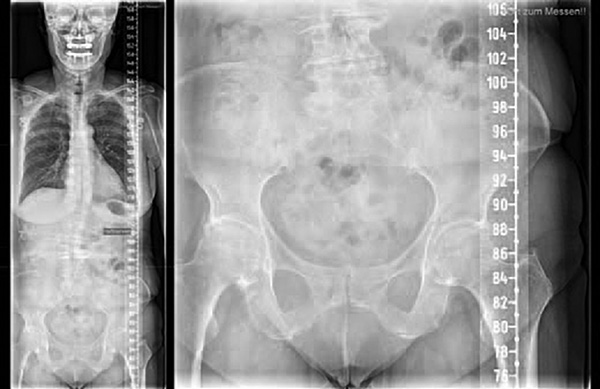

Zdjęcie rentgenowskie kobiety z artrozą biodrową, z prawej strony mocniej uwidocznioną niż z lewej. (Źródło: praktyka dra Meiera)

Oto obraz kobiety z artrozą stawu biodrowego, po prawej stronie wyraźniejszą niż po lewej. Wyraźnie widać, że występuje tu niewłaściwe ustawienie drugiego kręgu lędźwiowego, z którego wychodzi „nerw biodrowy”. Co by się stało ze stawem biodrowym, gdyby usunięto tę nieprawidłowość i sygnał mógłby być przekazywany optymalnie? Należałoby przypuszczać, że poprawiłaby się dostawa składników odżywczych do stawu. I tę ideę da się wdrożyć w praktyce. Efekt rzeczywiście jest taki, że ból ustępuje, ruchomość stawu się poprawia, a jakość życia człowieka wzrasta. Optymalnie tę metodę leczenia należy połączyć ze zdrową dietą, która unika uszkodzeń przez rodniki tlenowe. Niedobory minerałów należy wyrównać, a także zacząć odpowiedni program ćwiczeń i obciążeń. Dzięki temu da się zmniejszyć lub nawet całkowicie wyeliminować większość dolegliwości związanych z artrozą. Możliwość regeneracji przez centralny układ nerwowy to nieodkryty potencjał w medycynie. Przyszłość pokaże, jak będą się rozwijały terapie. Jednak już teraz można powiedzieć, że terapie naturalne zyskują na jakości, a nowoczesna medycyna, która jest niezbędna w wielu przypadkach, ale oferuje niewiele rozwiązań w przypadku chorób przewlekłych, stopniowo ustąpi na rzecz innych podejść. Czy operacja to „medycyna”, a regeneracja tkanek to „medycyna alternatywna”? A może wkrótce będzie na odwrót?